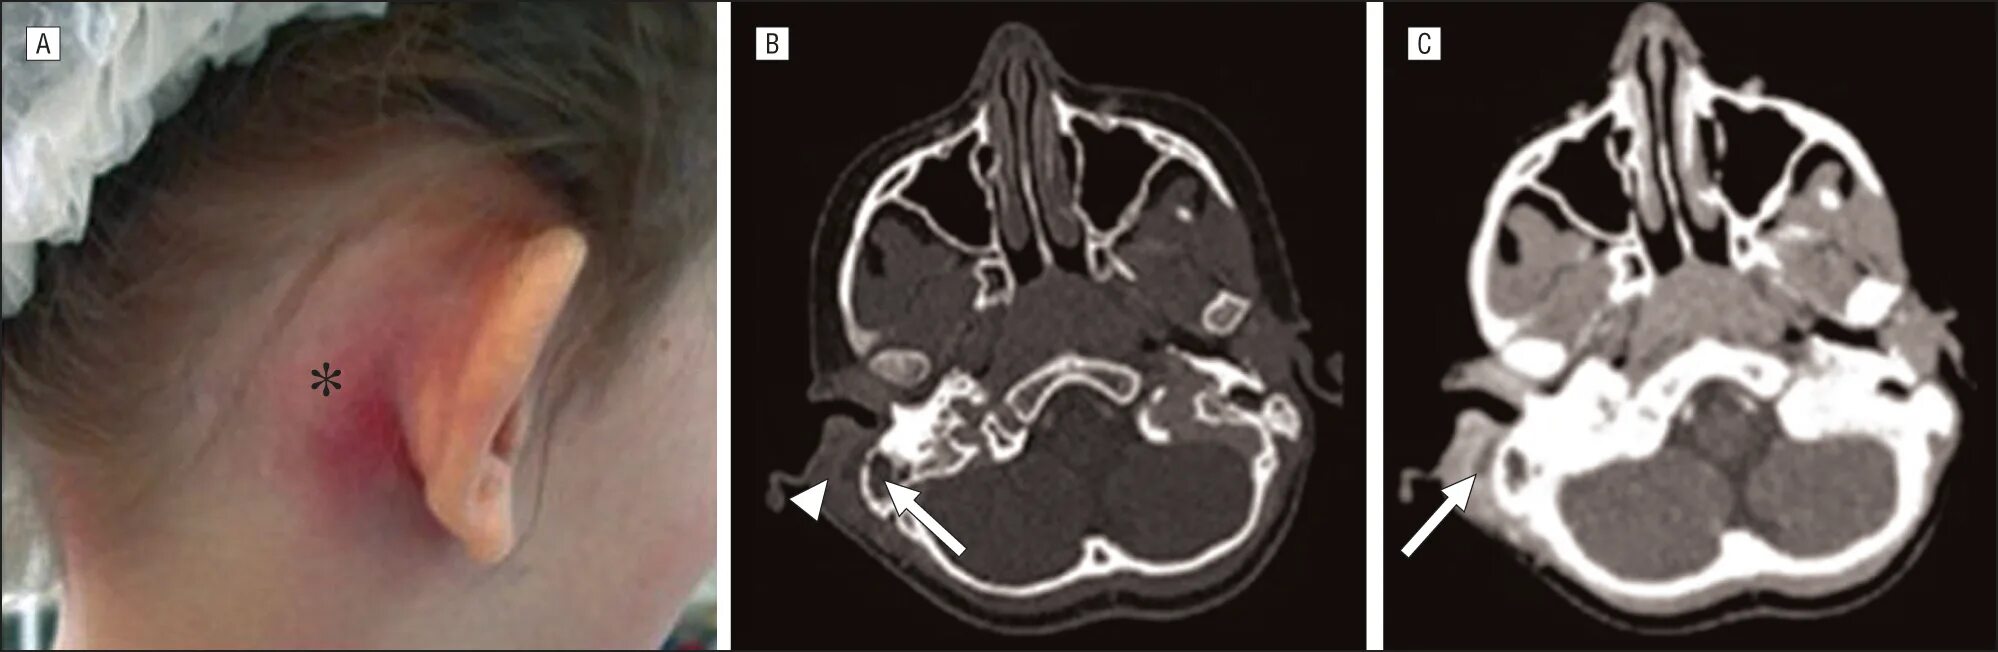

Побочный эффект кт